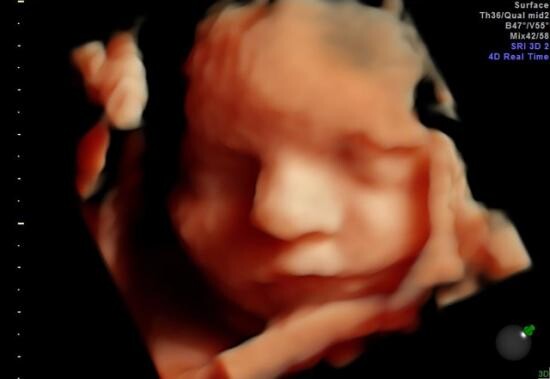

- badanie II trymestru (USG) wykonywane między 18-23 t.c.

Badanie to polega na ocenie anatomii płodu. Ponadto wykonana zostanie biometria i oszacowana masa płodu, sprawdzona funkcja łożyska oraz ilość płynu owodniowego.